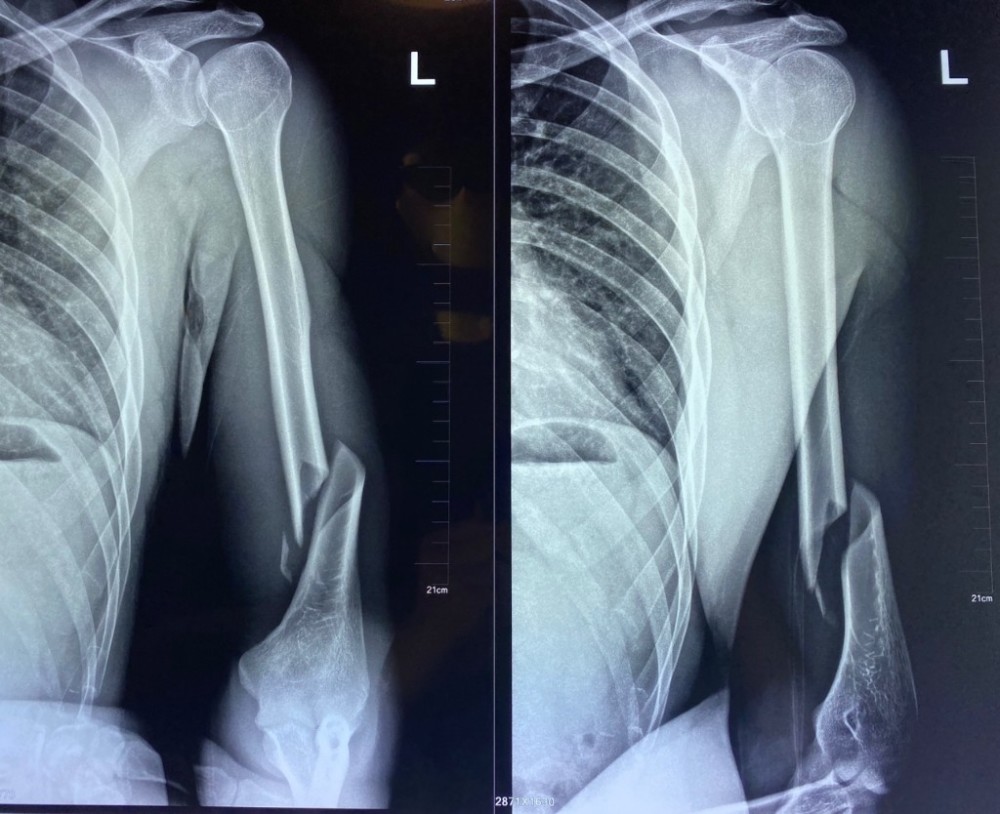

上臂离断

右手臂撕脱不完全离断伤